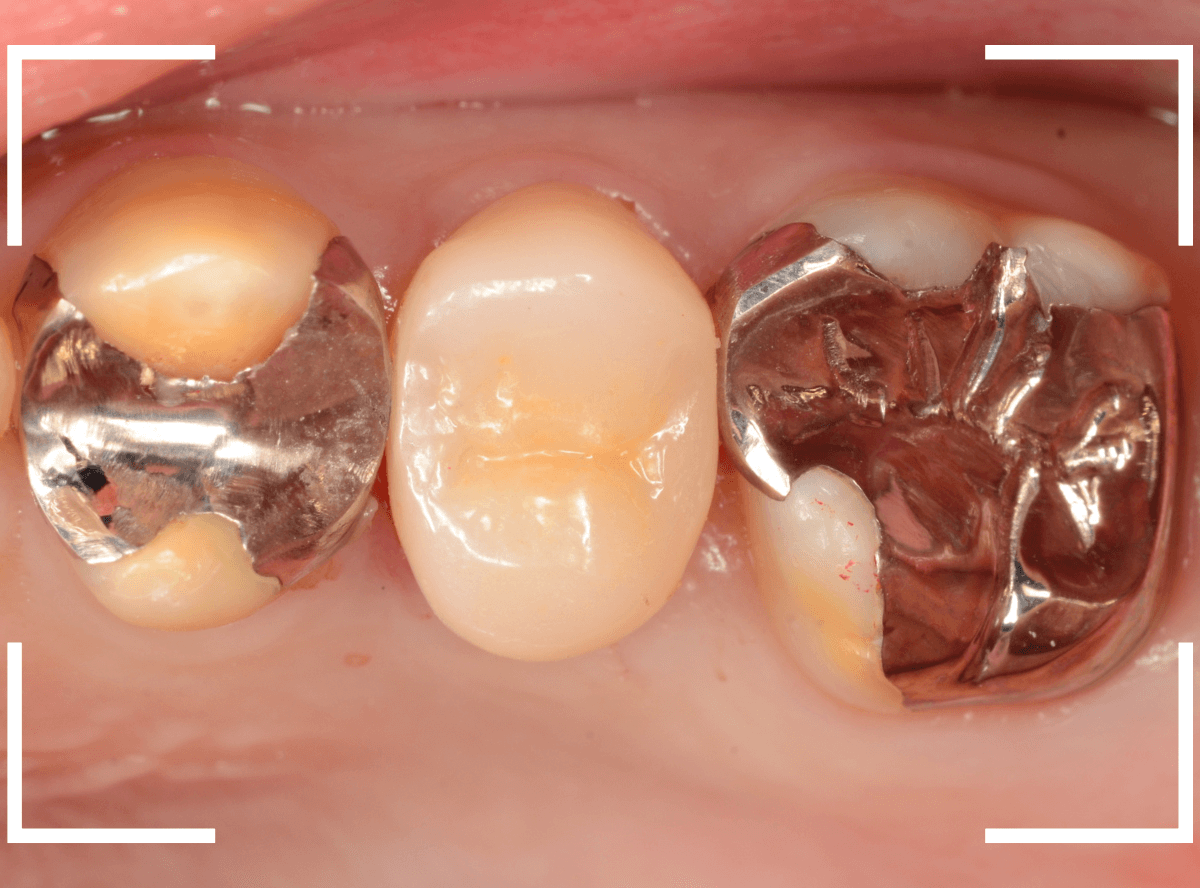

破折したCAD/CAM冠を、オール・ジルコニア・クラウンで修復

他院で、以前に入れたCAD/CAM冠(保険治療で作製できる白いさし歯)が破折した患者さんです。

CAD/CAM冠は、保険治療で比較的安価に製作できますが、銀歯に比べて壊れやすい、外れやすい、耐久年数が短いなどのデメリットがあるさし歯です。

中のメタルコアも透けて見えてますので、厚みもあまりない状態かと思われます。

それらの点を踏まえ、今回は、手前の歯と同時にセラミックで再製する事になりました。

まず、CAD/CAM冠を外します。

中のメタルコアも外して再製します。

歯を傷つけないように、時間をかけてそ~っとメタルコアを除去します。

メタルコアを除去して中を調べてみると、うっすらと虫歯になっていました。

このような状況は、入っているものを外してみないとわかりません。

治療前のCAD/CAM冠と、ジルコニア・クラウンの比較です。

CAD/CAM冠も見た目は白いですが、人工物っぽさが大きいのがわかると思います。

また、ジルコニアに比べると素材が脆弱で、長持ちさせるのは難しいです。